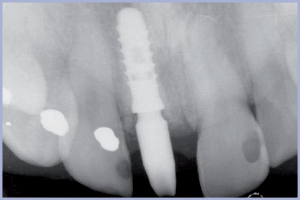

Al controllo a 18 mesi si apprezza salute e stabilità tissutale, armonia nella festonatura gengivale, papille trofiche, buona mimesi dell’unità dento-gengivale (figg. 36, 37). Il controllo radiografico conferma il mantenimento del livello osseo e dei picchi ossei interprossimali (fig. 38).

- Fig. 38 – Radiografia endorale di controllo a 18 mesi